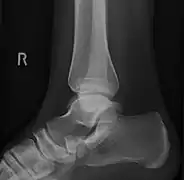

Radiological images

Type 2 on one foot (dark arrow) and type 3 on the other (white arrow)